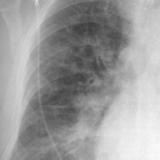

APE 1

Date: 11/05/2005

Views: 4072